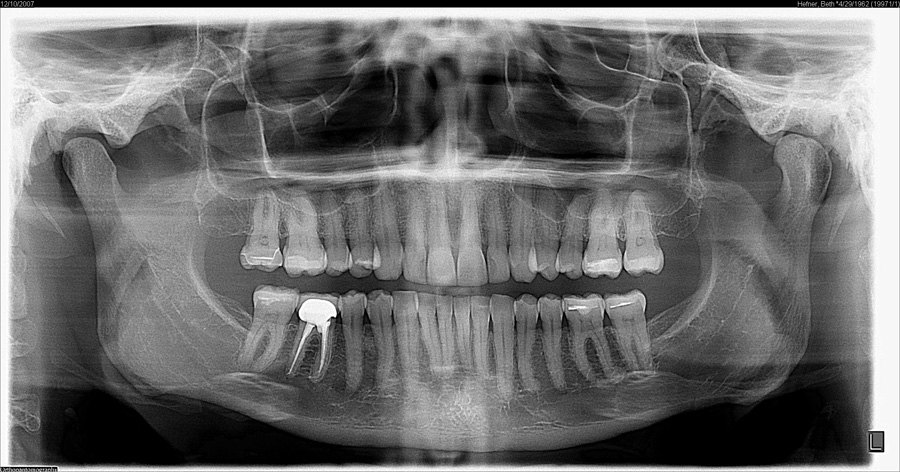

Our practice is among the first in the community to add a 3D extraoral imaging system to its office, revolutionizing patient treatment with highly detailed radiographs or X-rays. Having true-to-life 3D images produced by the device, called a CS 9300, helps Dr. Haddad provide quicker and more accurate diagnoses, improved treatment planning, and better patient care.

How are we using 3- 3-D technology in our office?

3-D technology has improved the accuracy of endodontic procedures by allowing our doctors to identify accessory canals, root fractures, apical abnormalities, and calcifications previously undetectable on 2-D X-rays.

3-D X-rays are valuable in minimizing the risk of nerve damage by accurately locating the position of the inferior alveolar canal in the lower jaw and identifying other previously undetectable anatomical variabilities. While we do not perform oral surgeries in-house, this technology is crucial in aiding the dental professionals we collaborate with to avoid possible complications during and after surgical procedures.

This technology provides the advantages of high-resolution, relatively low radiation dose, and the ability to target a specific area evaluation, it is an industry-leading system designed to dramatically enhance treatment planning while delivering fast, accurate results for enhanced patient communication.

Because the CS 9300 system allows our doctors to target the exact area for exposure, dental patients are exposed to significantly less radiation when they receive an x-ray. This means other tissues around the mouth will not be unnecessarily irradiated. The system combines speed (taking X-ray images in as little as 12 seconds), image quality, and precision placement to dramatically reduce the need for retakes.

With 75-90% smaller radiation dose than conventional scans of a similar type, the CS 9300 helps us adhere to the ALARA Principle – or, ‘As Low As Reasonably Achievable’ – which we follow to ensure every precaution is taken to minimize patient exposure to radiation when obtaining the necessary diagnostic images needed for treatment planning.

With a low radiation dose and precise, crystal-clear 3D panoramic images, the CS 9300 offers unprecedented anatomical insight into specific dental regions of interest to help diagnose more accurately and treat with confidence. Benefits of the CS 9300 include: